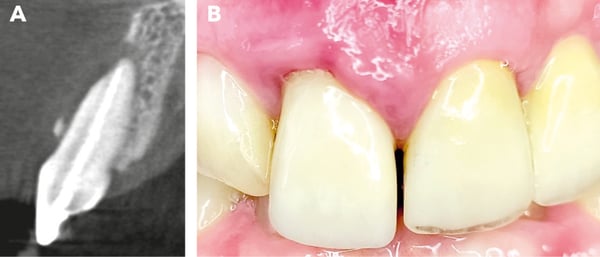

Initial clinical situation. The sectional image of the CBCT, along with the recession on tooth 11, reveals a class III defect according to Kim et al. [3]. The mucosa appears inflamed, and an extensive loss of the buccal alveolar wall is visible

Final situation. After 4 months, when the surgical site was reopened (Figure J), a completely regenerated alveolar ridge was revealed. The alveolus showed complete radiological regeneration (Figure K), allowing for straightforward implant placement. Figure L illustrates the final prosthetic restoration with irritation-free mucosa conditions after one year